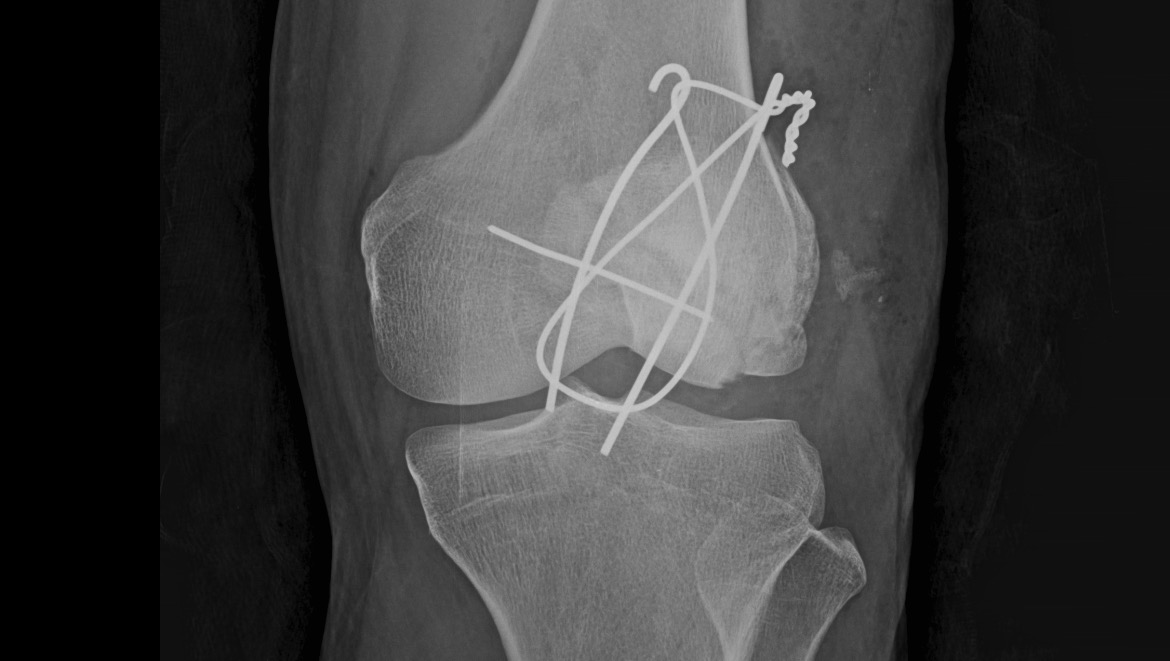

Salí del quirófano con 3 clavos y un alambre para unir los pedazos de mi rótula, muchos puntos y mucho dolor.